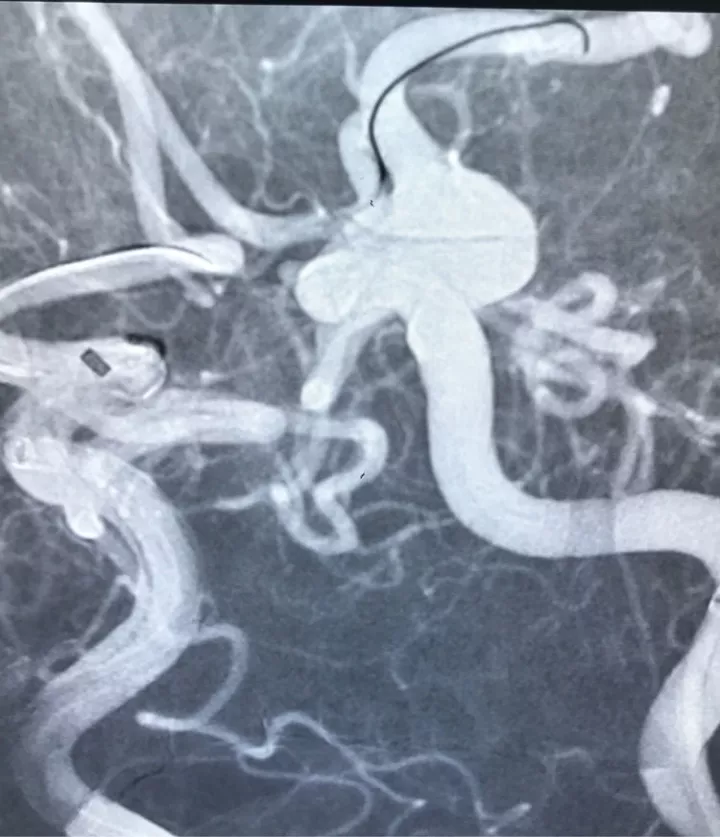

男,49岁,蛛网膜下腔出血

左侧后交通动脉瘤,胚胎型大脑后动脉

3D

局部观,宽颈,涉及颈内动脉和后交通动脉

椎动脉造影见左侧大脑后动脉P1段很细

栓塞的关键是既要保持颈内动脉通畅,又要保持后交通动脉通畅。双导管单纯填塞;通过颈内动脉释放支架灯笼技术辅助是可选的方案。本例是通过后交通动脉释放支架,利用支架摆尾技术(half-T)来进行栓塞。支架导管塑型

Enterprise4.5×22支架半释放,支架尾端的有效段能恰好覆盖全瘤颈

支架完全释放

释放后的造影。突入颈内动脉和后交通动脉内的弹簧圈被压入瘤体内

继续填塞,后面就简单了。最后的结果,一共用了四枚弹簧圈,栓塞致密,瘤体及破口都不显影了